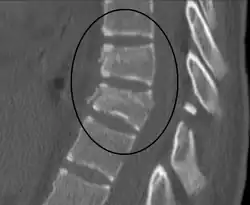

| A Chance fracture of T10 and fracture of T9 due to a seatbelt during an MVC. | |

A Chance fracture is a type of vertebral fracture that results from excessive flexion of the spine.[8][9] Symptoms may include abdominal bruising (seat belt sign), or less commonly paralysis of the legs.[4][10] In around half of cases there is an associated abdominal injury such as a splenic rupture, small bowel injury, pancreatic injury, or mesenteric tear.[3][5] Injury to the bowel may not be apparent on the first day.[11]

The cause is classically a head-on motor vehicle collision in which the affected person is wearing only a lap belt.[2] Being hit in the abdomen with an object like a tree or a fall may also result in this fracture pattern.[12][10] It often involves disruption of all three columns of the vertebral body (anterior, middle, and posterior).[7][6] The most common area affected is the lower thoracic and upper lumbar spine.[6] A CT scan is recommended as part of the diagnostic work-up to detect any potential abdominal injuries.[5] The fracture is often unstable.[1]

A CT scan of the chest, abdomen, and pelvis is recommended as part of the diagnostic work-up to detect any potential abdominal injuries.[5][10] MRI may also be useful.[10] The fracture is often unstable.[1]